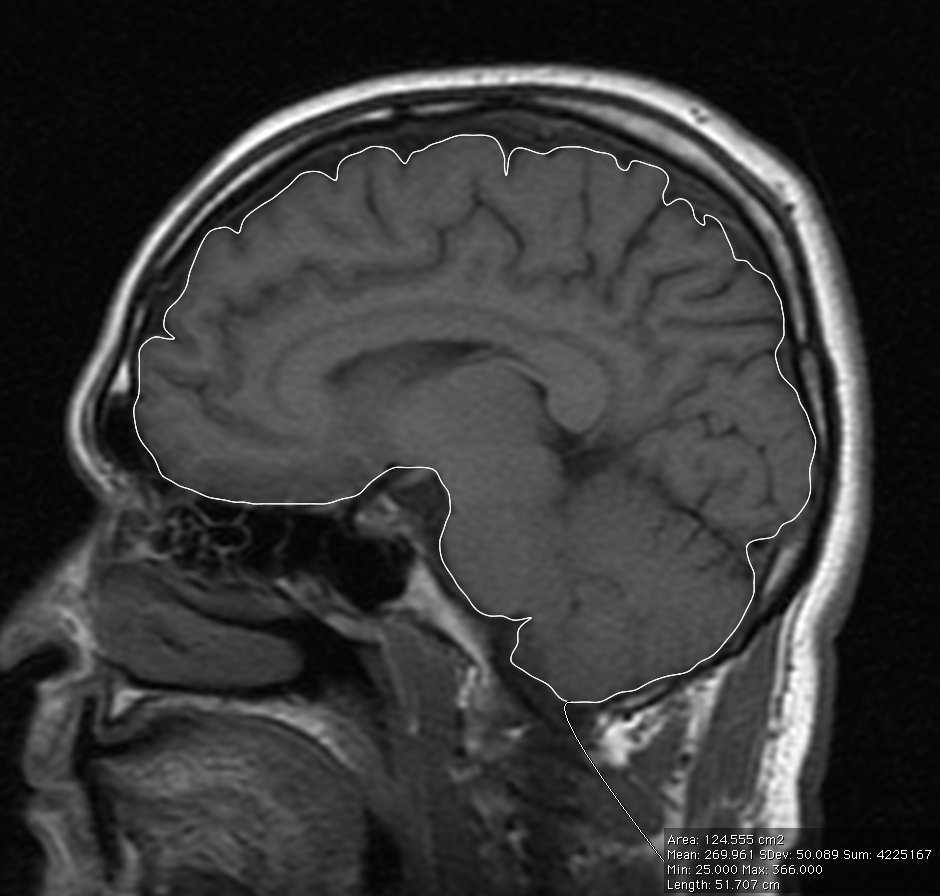

This study aimed to determine the total intracranial volume, total brain volume and total intracranial volume to total brain volume ratio among the male and female subjects in normal healthy subjects aged 40 years old and above. This was a retrospective study involving 58 subjects aged from 41 to 77 years old. The study was approved by the institutional review board. Magnetic resonance imaging of the brain performed using General Electric Signa Horizon LX 1.0 Tesla scanner. Magnetic resonance images were obtained in T1 sagittal and axial sections with 5-millimetre thickness with 2-millimetre gap. The images acquired were stored in the hospital’s Picture Archiving and Communications system and viewed using Osirix image viewer version 3.2.1. A single observer validated by an experienced neuroradiologist with more than 10 years’ experience performed volumetric analysis. Mean (SD) of total intracranial volume was 1397.06cm3 (132.51cm3) for all subjects. The mean total intracranial volume for male subjects was 1496.12cm3 (100.08cm3). For female subjects, the mean total intracranial volume was 1310.79cm3 (90.34cm3). The mean total brain volume for all subjects was 1245.29cm3 (125.34cm3). The mean total brain volume for the male subjects was 1338.05cm3 (91.96cm3). For the female subjects, the mean total brain volume was 1164.49cm3 (89.61cm3). Mean total brain to intracranial volume ratio for all subjects were 0.8911 (0.0245). Mean total brain to intracranial volume ratio for male subjects was 0.8946 (0.0276). Mean total brain volume to total intracranial volume ratio for female subjects was 0.8881 (0.0214). This study showed no significant difference in mean total intracranial volume, mean total brain volume and total brain volume to total intracranial volume ratio between male and female. However, the study obtained valuable normative data for estimation and predicting future degenerative events in our population